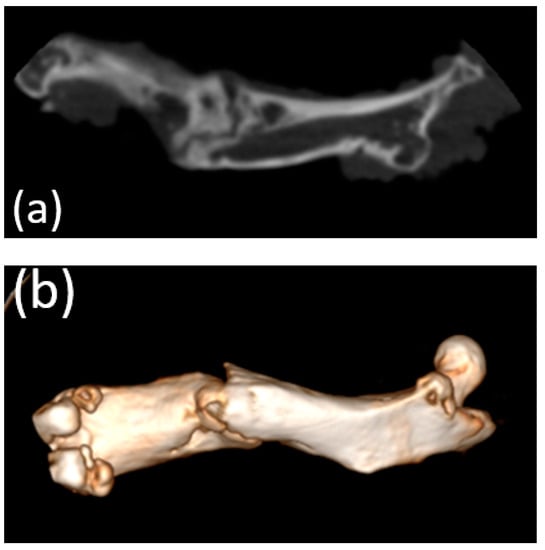

3.5. Micro-CT